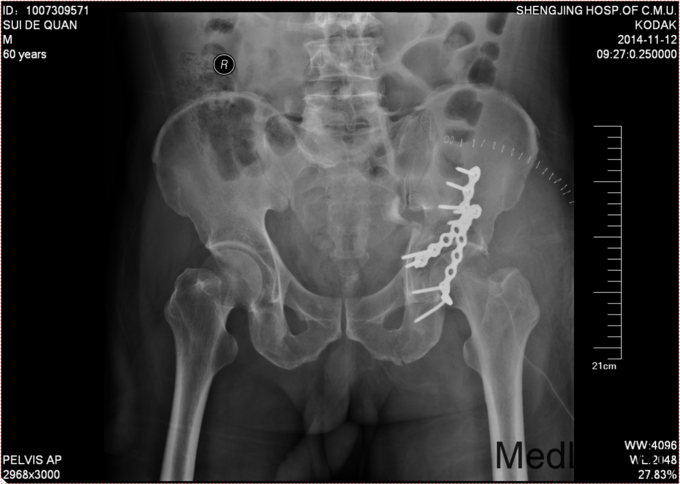

入院后急诊行左髋关节脱位复位术,左胫骨结节骨骼牵引术。术后牵引7公斤,完善相关检查后,全麻下行左髋臼骨折切开复位内固定术。术后患者生命体征平稳,卧床。术后14天拆线后出院,回当地医院继续治疗。

患者术后3个月可以拄拐下地行走,口服吲哚美辛预防异位骨化。